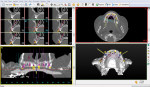

The new denture was duplicated in a mixture of 30% barium sulfate to acrylic resin powder by weight and utilized as a radiographic stent. A CBCT was done while the patient wore the radiopaque duplicate denture. The digital imaging and communications in medicine (DICOM) files from the CBCT were imported into implant planning software (SIMPLANT®, DENTSPLY Implants, dentsplyimplants.com). The surgical plan was developed and then sent to the software vendor for fabrication of a soft-tissue–supported surgical guide for use in a flapless surgical procedure. The surgical guide was made compatible with the Tapered Navigator® surgical kit (Biomet 3i, biomet3i.com) (Figure 4).